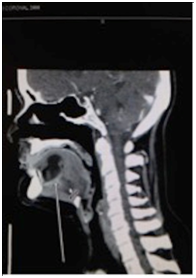

A 57-year-old Caucasian female was flown from a remote location to the emergency department for emergent consultation for a possible sublingual abscess. She complained of increasing right jaw pain and difficulty opening her jaw. The patient was afebrile and non-toxic appearing. Physical examination revealed right temporomandibular joint pain upon palpation, trismus, and slight fullness of the oral tongue and floor of the mouth. Initial laboratory data was within normal limits and was not significant for an acute inflammatory process. Computed tomography with intravenous contrast was performed and revealed a 2x3 centimeter intralingual hypodense fluid collection possibly representing an abscess (Figure 1). A trans-oral needle aspiration was performed to determine the nature of the cystic lesion. Approximately three cubic centimeters of yellow, thick, cheesy material was aspirated and sent for cytology. The patient was then discharged with a presumed diagnosis of dermoid cyst, dietary modifications for her temporomandibular joint syndrome, prophylactic oral clindamycin, and recommendation to return for surgical excision of the cyst. One week later, the patient returned to the emergency department complaining of increased swelling of the oral tongue and floor of mouth. The patient once again remained afebrile and non-toxic appearing. A repeat trans-oral needle aspiration revealed purulence and the patient was subsequently admitted to the hospital for intravenous ampicillin/sulbactam and scheduled for excision of the cyst at the next available operating time.

Figure 1(a-c) Pre-operative CT images with intravenous contrast demonstrating the intralingual fluid collection consistent with presumed abscess but post-operatively confirmed by pathology as a dermoid cyst.